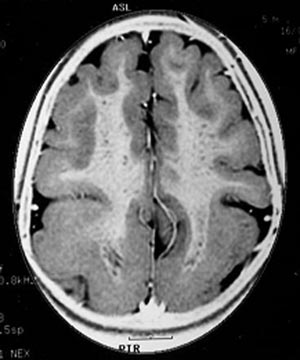

Figura 104 - Ressonância nuclear magnética de uma criança portadora de malformação grave do córtex cerebral nos 2 hemisférios cerebrais (lissencefalia) e crises epilépticas de difícil controle